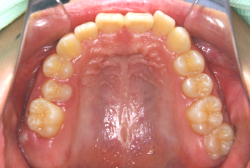

急速拡大装置を1日1回装置の中央にある拡大ネジを、ご自身で回して頂くことで25日間くらいかけて、6mmほど拡大しました。拡大後は、上顎の前歯の隙間が広がっていることがお分かりいただけると思うのですが、土台の骨ごと広がるのでこのような隙間ができます。その後1年半くらいマルチブラケット装置を使用して、全体の修正を行いました。

結局、歯の本数を減らすことなく、すべてご自分の歯を残して正しい配列にすることができました。このケースの場合、2009年10月より拡大と経過観察を行い、2012年3月より1年2ヶ月マルチブラケット装置を装着、2013年5月に治療を終了しました。2段階で行う治療としては短期間で終了しているケースと思います。